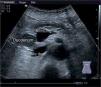

The disease started 3 months prior to her admission when the patient presented jaundice, choluria, asthenia, adynamia, with weight loss of approximately 10kg, over the same period. On admission she presented jaundiced skin and sclera. General examination showed no pathological signs. The laboratory tests reported total bilirrubin 15.5mg/dl, direct bilirrubin 8.9mg/dl, alkaline phosphatase 1860u/l, GGT 2217u/l, with albumin 1.4g/dl. Abdominal ultrasound reported dilation of the intra and extrahepatic bile duct, common bile duct 17.8mm, with hyperechoic images inside relating to biliary sludge. The bile duct had heterogeneous predominantly hyperechoic content due to biliary sludge. The pancreatic gland had a heterogeneous ultrasound pattern, duct of Wirsung 3.8mm, thickening in the second portion of the duodenum, related to a probable duodenal neoplasm (Fig. 1). Upper endoscopy showed no alterations in the stomach. It was not possible to pass the endoscope beyond the first portion of the duodenum due to stenosis of the lumen at this level, no ulcerated mucosa or areas showing tumour or infiltration. Percutaneous transhepatic cholangiography was performed, showing dilated bile ducts, with some segmentary dilatation associated with peri-cholangitic abscesses. During this procedure an 8.5 Fr catheter was placed, which was passed up to the duodenal lumen (Fig. 2). Axial computed tomography with pancreatic protocol showed an enlarged liver with left lobe predominance, homogeneous parenchyma and large dilation of the intrahepatic bile duct, and pancreas with homogeneous attenuation pattern. Wall thickening was observed in the duodenum that reduced its lumen by approximately 90%, which was enhanced by contrast medium, with a plane of separation with the pancreatic head, relating to a tumour of approximately 4cm of the ampulla of Vater. Endoscopic ultrasound was performed showing a lesion of 41mm×31mm in the pancreatic head, which extended towards the periampullary region and duodenal wall; the vascular structures were intact. No adenopathies were identified (Fig. 3). Aspiration biopsy reported moderately differentiated adenocarcinoma of the ampulla of Vater. Enteral support was decided after nutritional assessment to improve the patient's condition and she was scheduled for laparoscopic pancreatoduodenectomy on 1 June 2015.